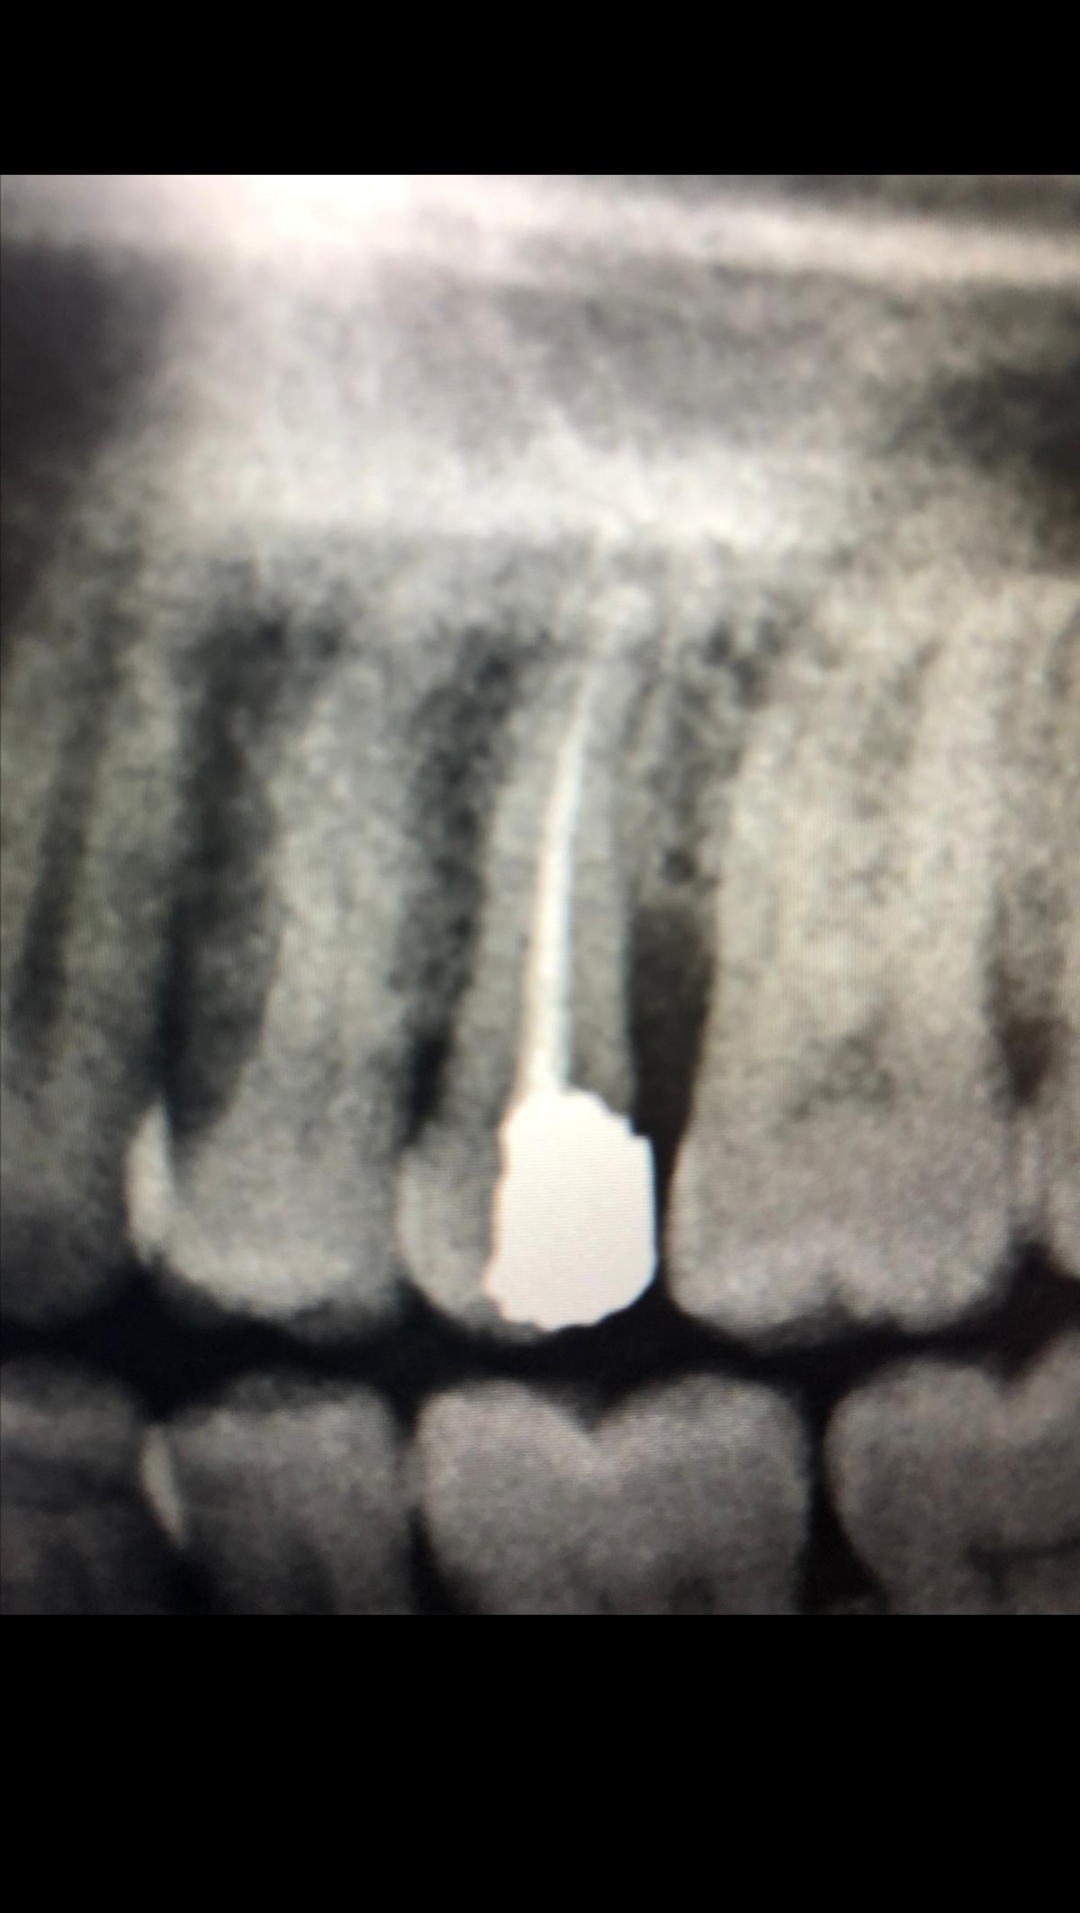

معرفة المشكلة في صور الاسنان